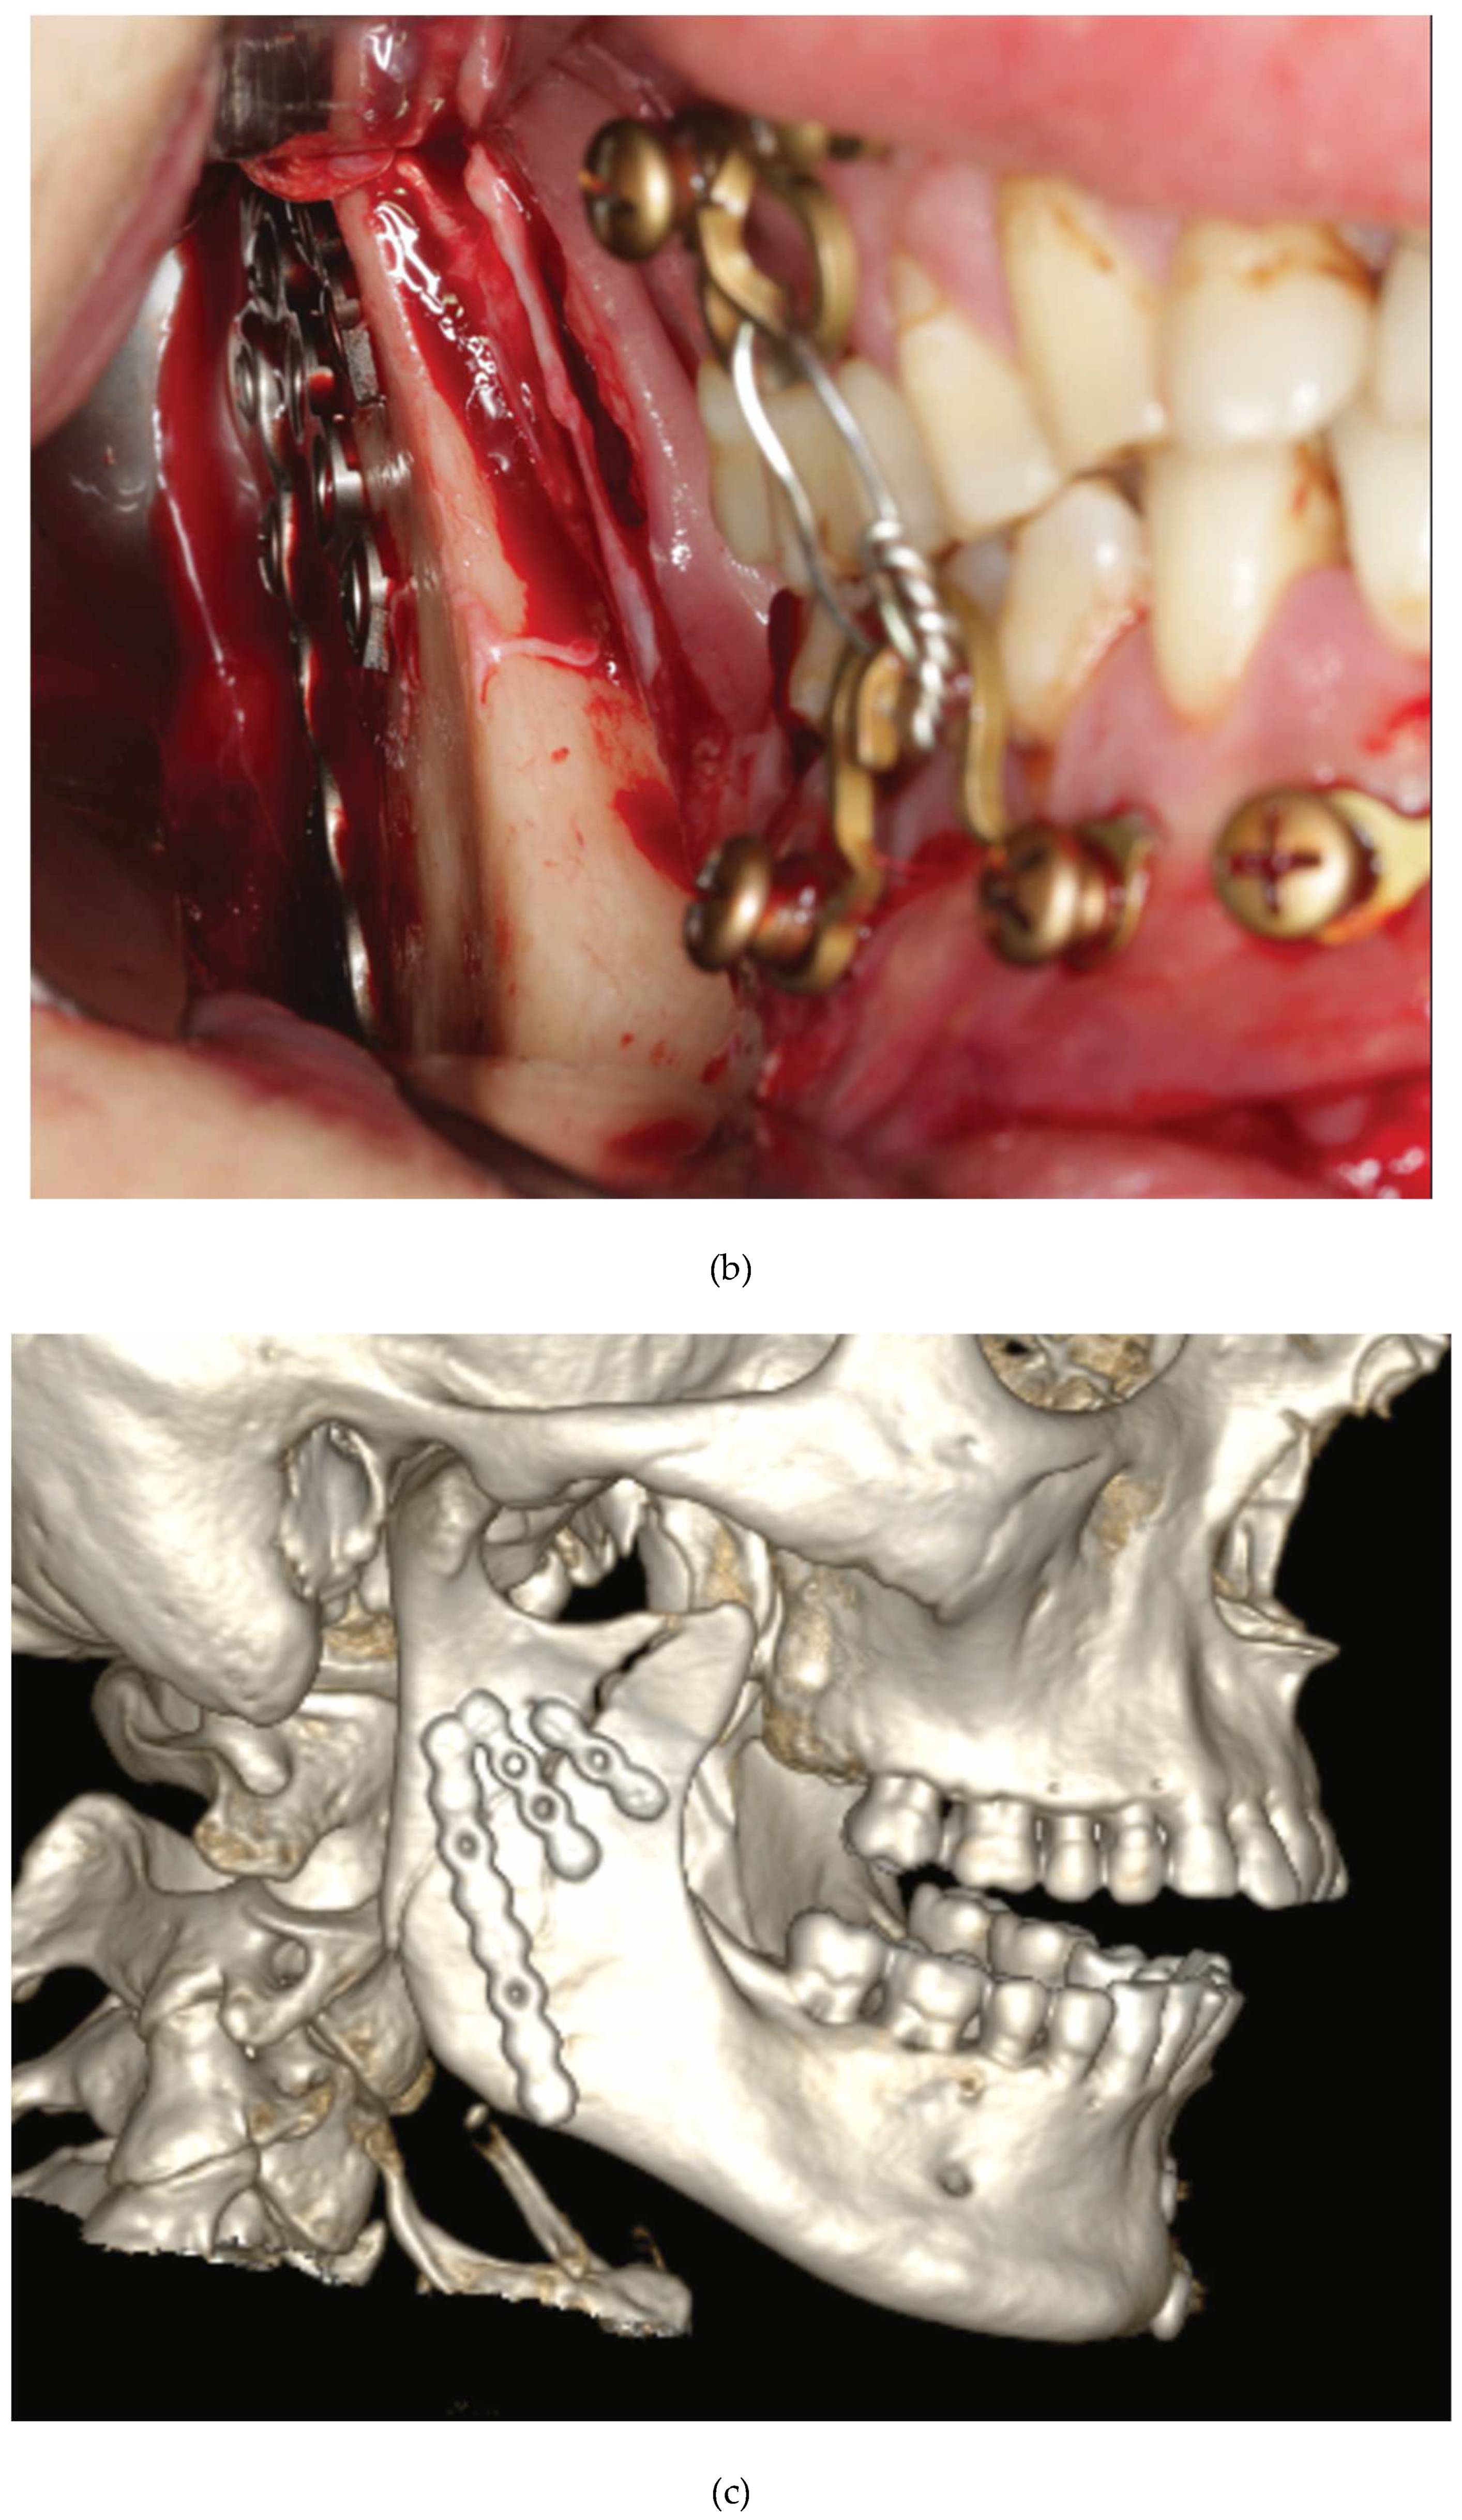

Figure 3.

Case Example – Neglected dentition unsuitable for circumdental wire fixation of arch bars in a self-inflicted gunshot injury. Use of an alternative to conventional arch bars: locking adaptation plates secured with self-tapping Locking bone screws into the alveolar rims, mounted with MMF nuts and interconnecting wire ligatures hooked over the protruding MMF nuts. Notice: bone fixation with screws inserted along mucogingival junction zones. Source/origin of Figure 3: Photograph collection – C.P. Cornelius